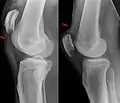

Quadriceps tendon rupture in plain X-ray

Quadriceps tendon rupture in plain X-ray: Incomplete rupture with haematoma in tendon.